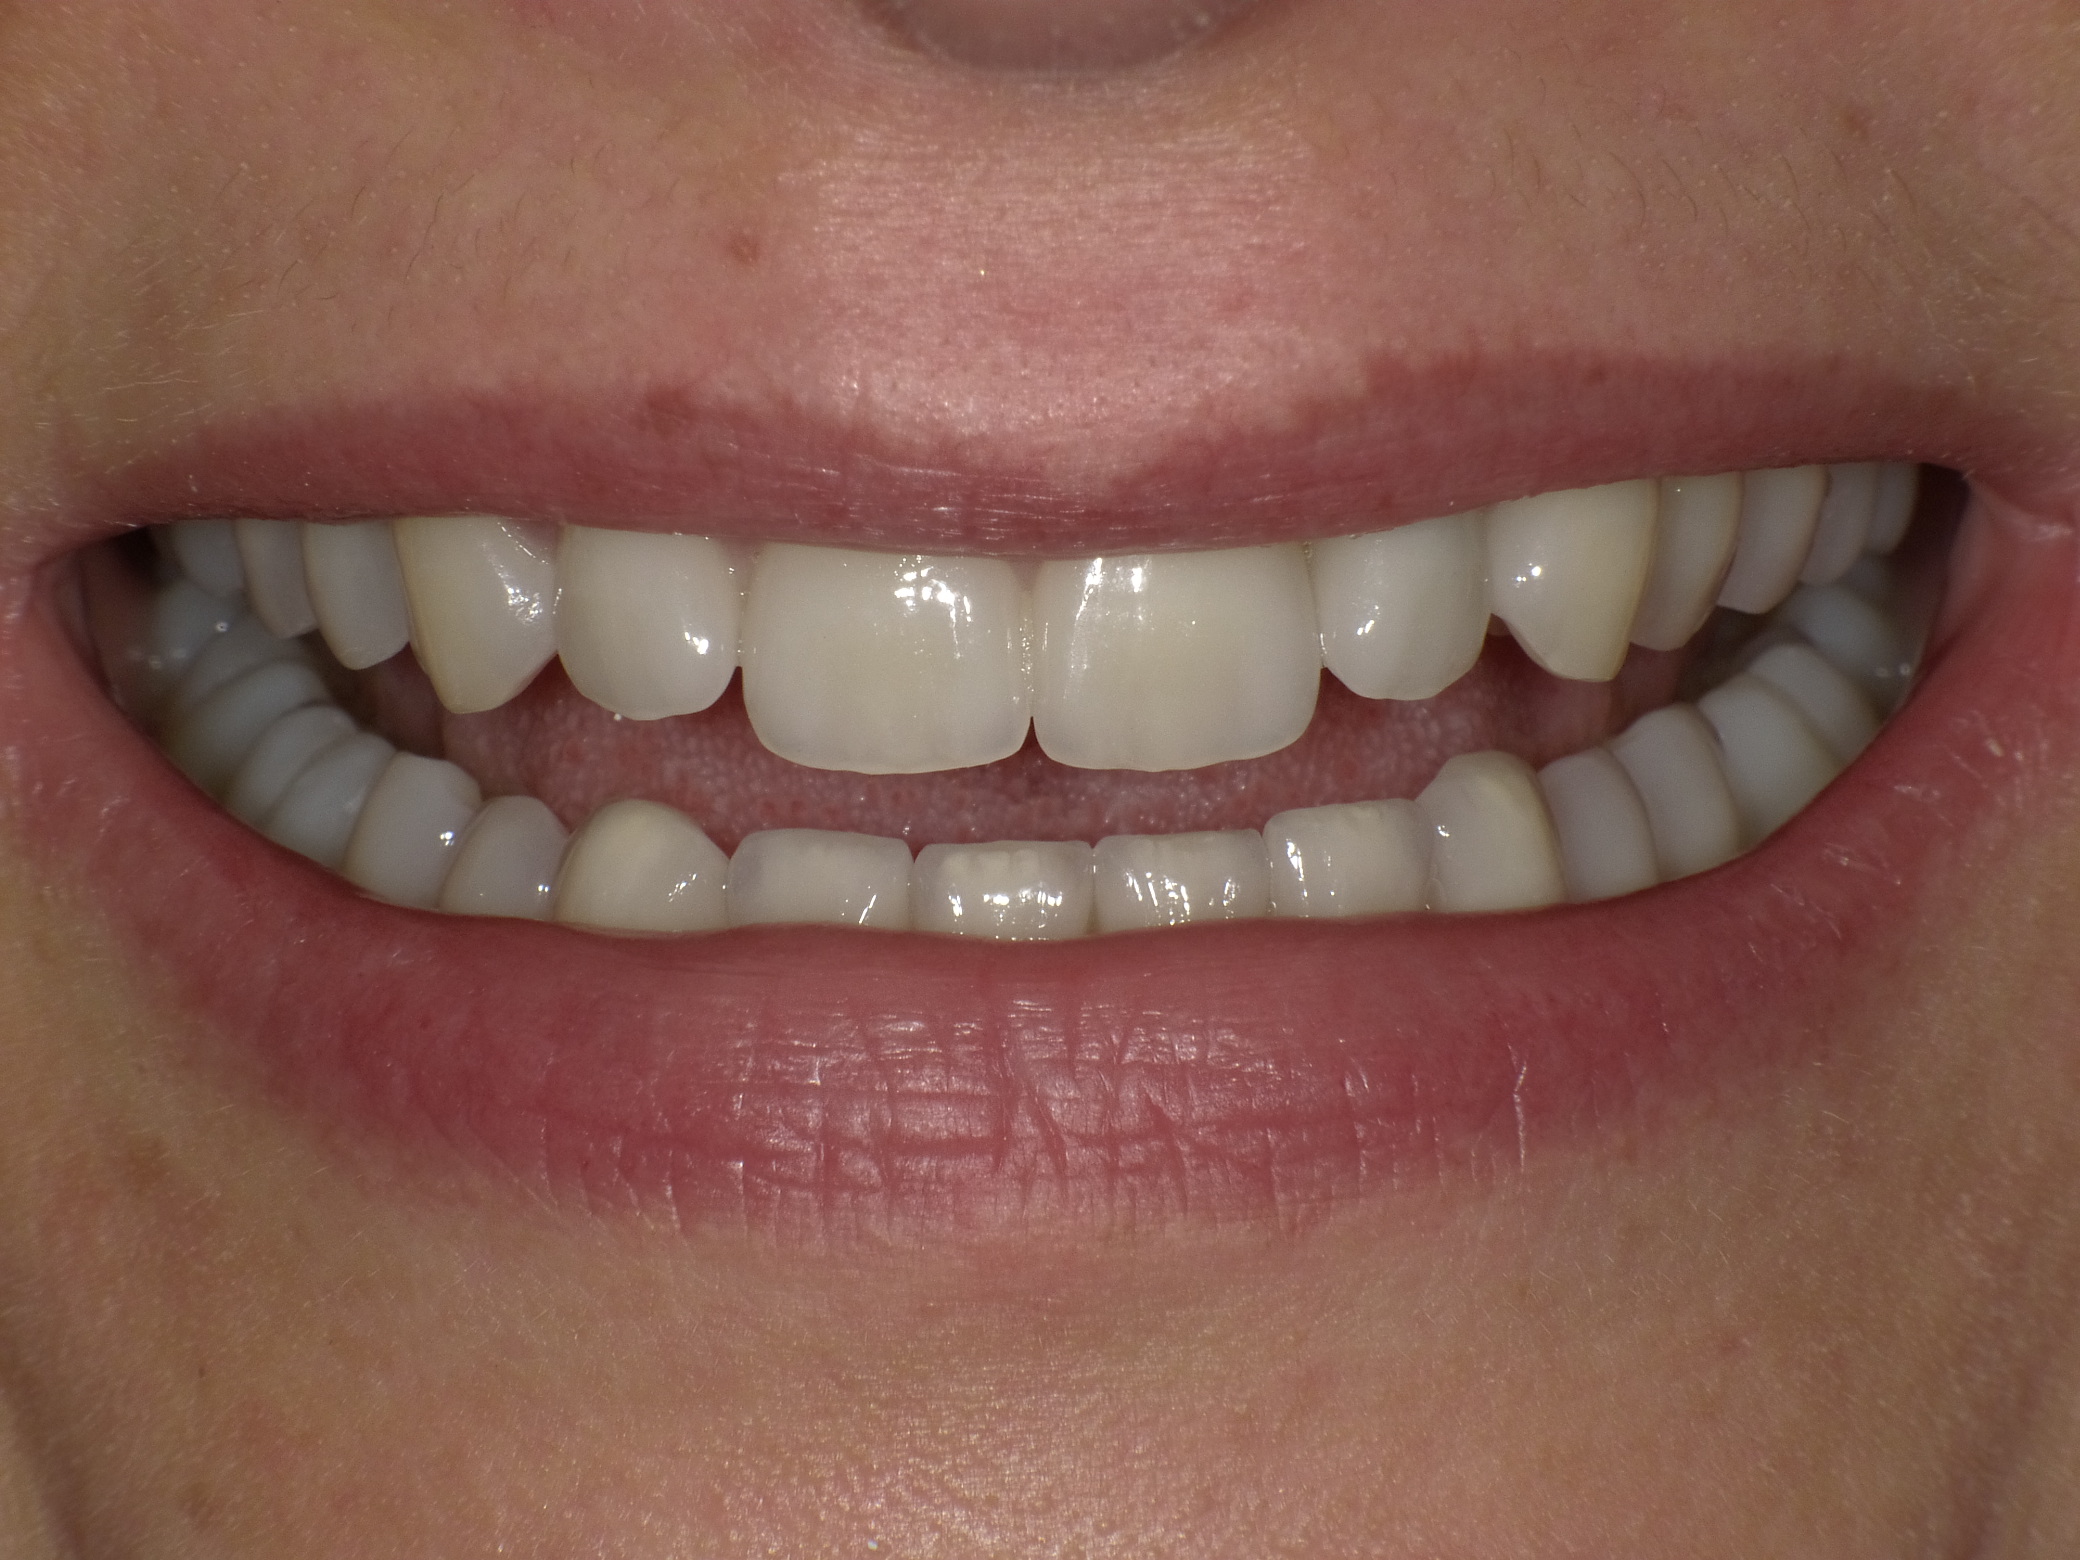

Abradierte, gelbliche Zähne mit vielen Kunststoff-Füllungen und Kronen, die der Patientin nicht gefallen haben

Leuchtende Zähne durch vollkeramische Veneers und Teilkronen in nur 2 Terminen

Nachher: Leuchtende Zähne durch vollkeramische Veneers und Teilkronen in nur 2 Terminen